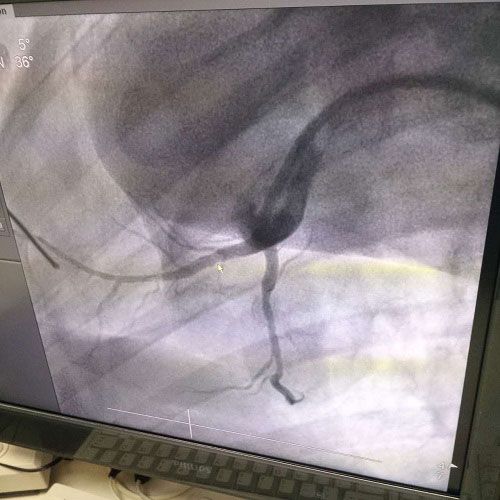

生物全降解鎂合金藥物洗脫支架是我由公司自主立項研發、主(zhu)要(yao)工(gong)藝(yi)技(ji)術(shu)完(wan)全(quan)自(zi)主(zhu),具(ju)有(you)完(wan)全(quan)自(zi)主(zhu)知(zhi)識(shi)產(chan)權(quan)。並(bing)且(qie)可(ke)行(xing)性(xing)強(qiang),前(qian)期(qi)研(yan)發(fa)基(ji)礎(chu)紮(zha)實(shi),市(shi)場(chang)需(xu)求(qiu)迫(po)切(qie),實(shi)施(shi)風(feng)險(xian)可(ke)控(kong),屬(shu)全(quan)球(qiu)同(tong)行(xing)業(ye)領(ling)先(xian)技(ji)術(shu),填(tian)補(bu)國(guo)內(nei)技(ji)術(shu)發(fa)展(zhan)空(kong)白(bai),符(fu)合(he)國(guo)家(jia)產(chan)業(ye)發(fa)展(zhan)政(zheng)策(ce),社(she)會(hui)、經濟效益巨大。目前鎂合金藥物支架已進入動物實驗階段,植入動物體內一個月之後效果良好。